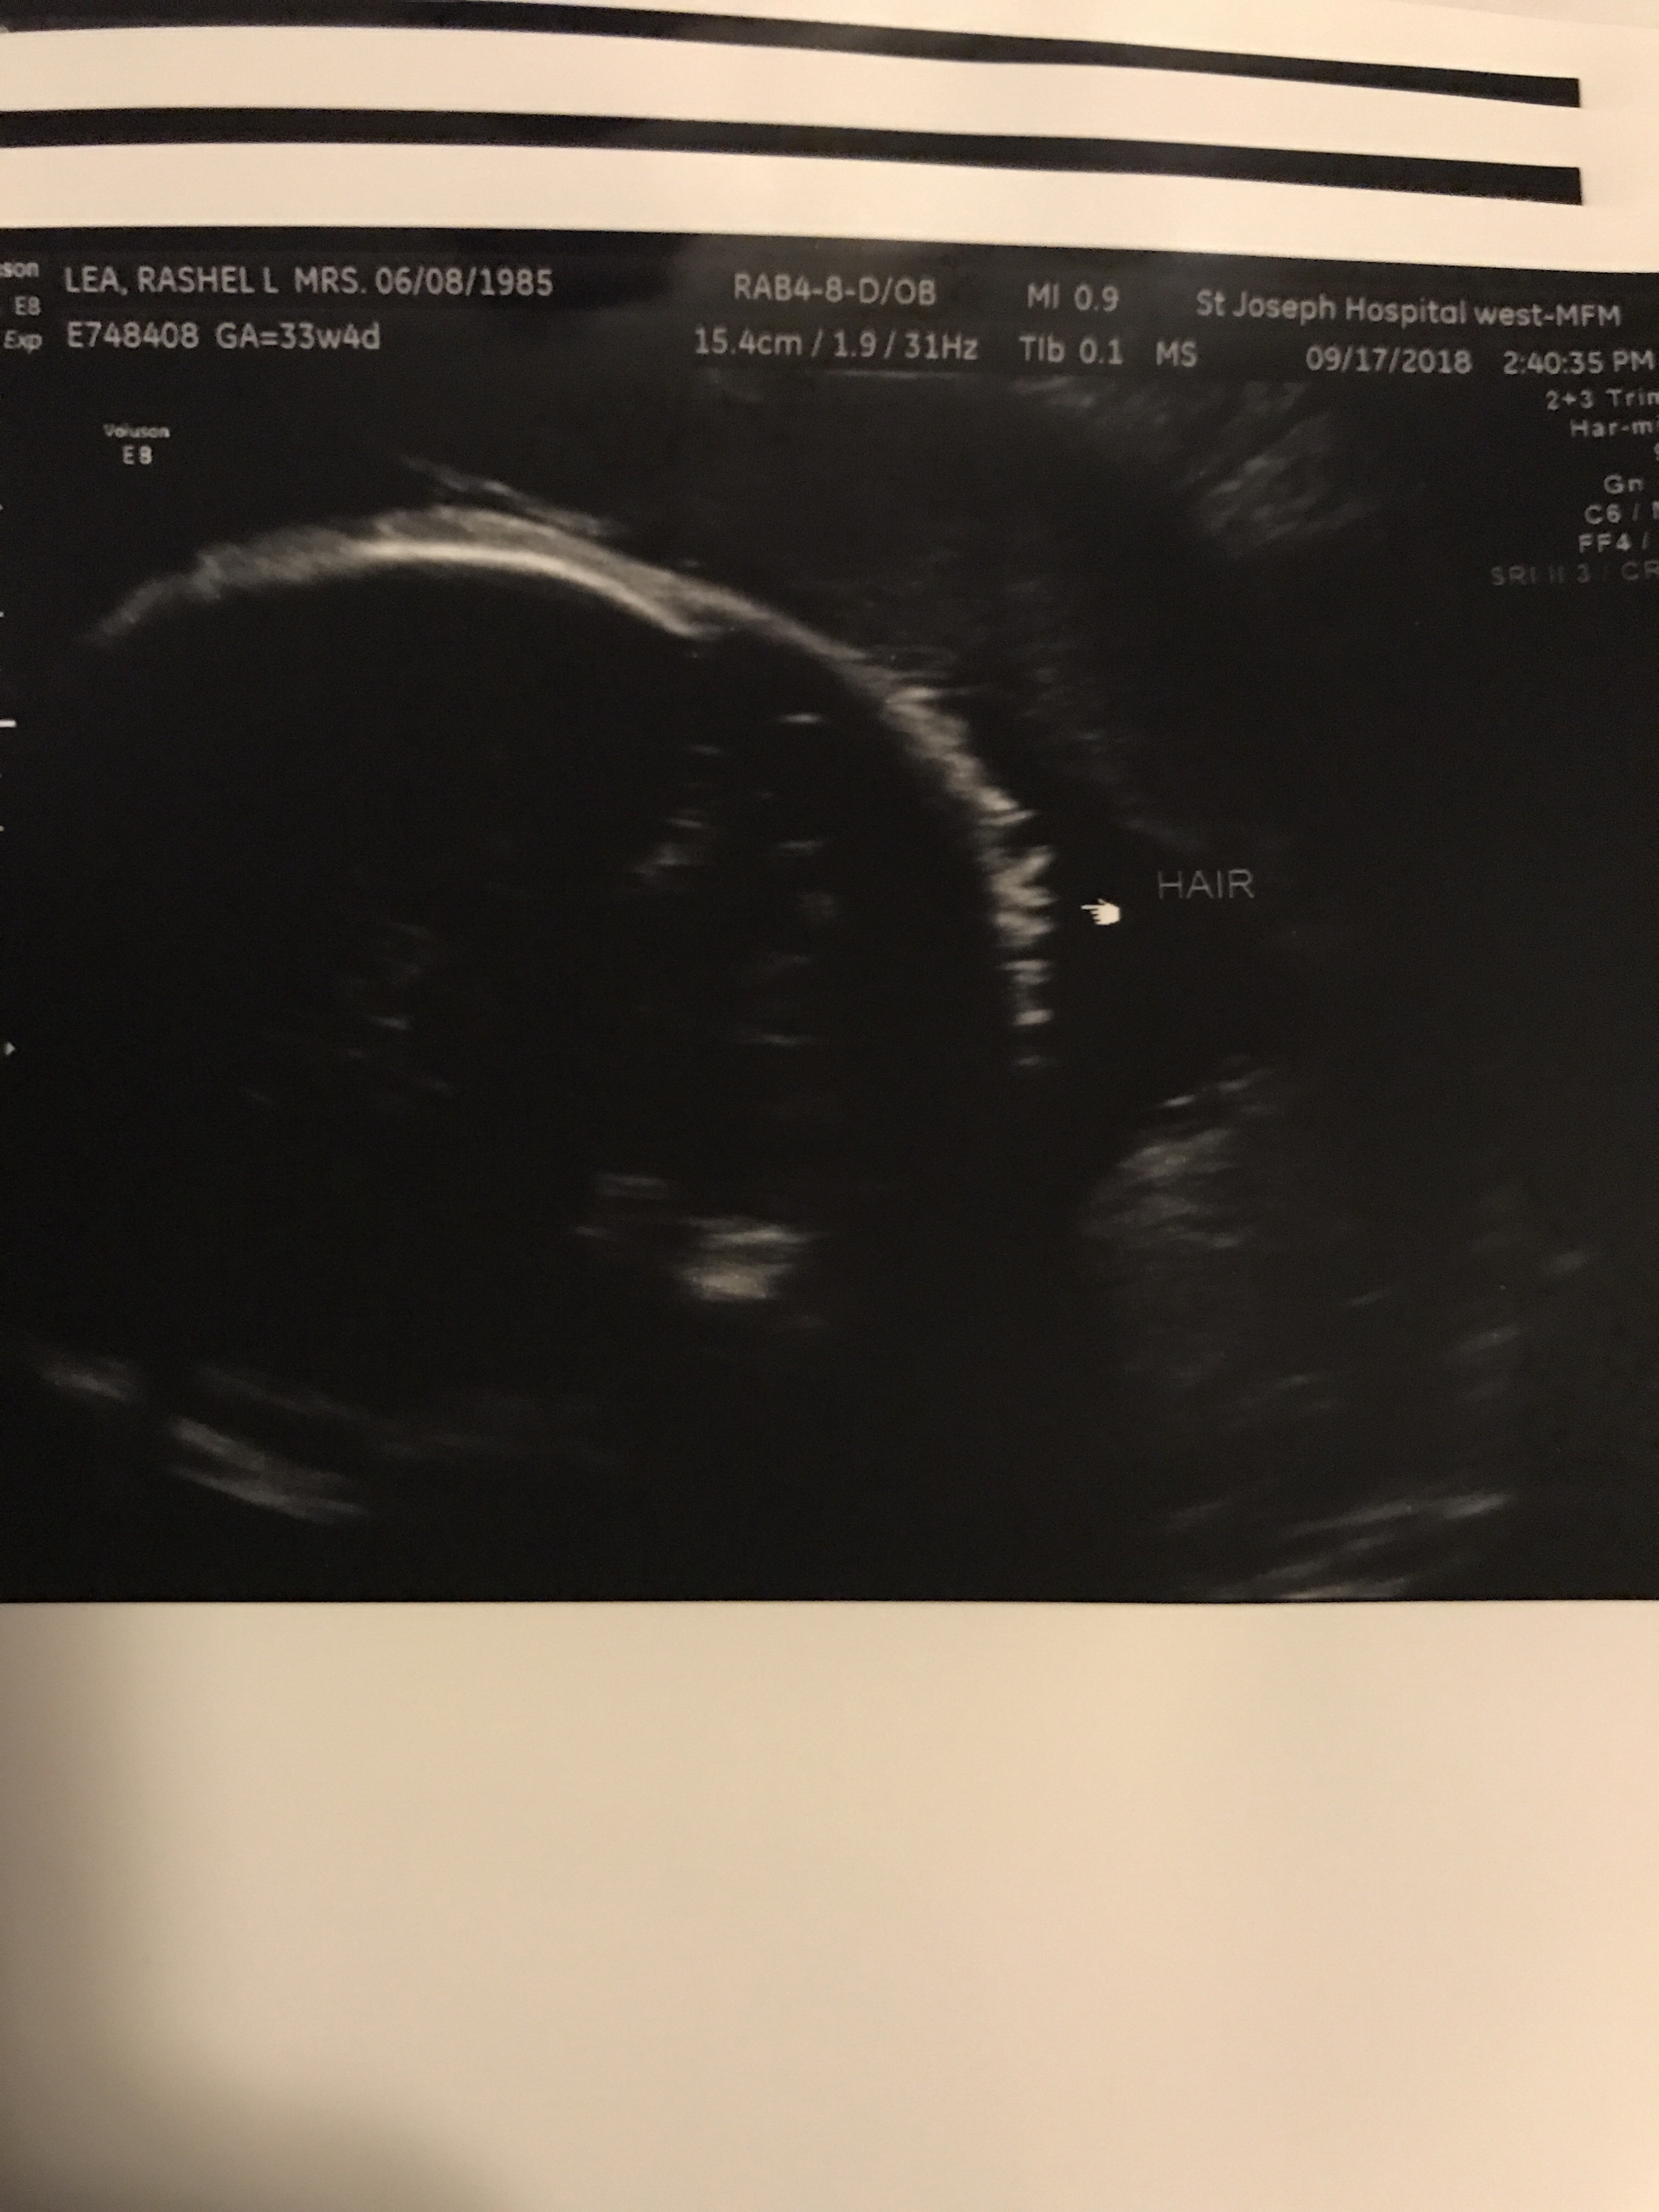

Things are going well. Baby B is enjoying life on the inside. He likes to kick and play often. We love our fun time together as long as it’s not in the middle of the night. Haha. I’m definitely getting more stretching ligaments if you have had them you know they are zero fun. If you haven’t let me try to explain. It’s basically like you move from any normal position and all the sudden it feels like someone has a huge sharp knife and they are stabbing you with it. Every time you try to move or adjust the knife is being twisted viciously. This happens always by surprise you never know when to expect the knife fight but let me tell you I always lose lol. I’m still eating all my ice! I love love LOVE crunching on ice. I’m definitely getting more round and I freaking love it! People can tell now so that’s great. I look super cute in clothes! Now out of clothes not so much… I have had a few Braxton-Hicks from time to time usually when I’m busy at work and not drinking enough water. I asked Dr. Google since it seemed a bit early and of course he said it’s normal when you have had a few pregnancy’s. I guess number 5 counts as a few! I also followed up with my real dr who also said yep it’s fine! I still feel super lucky I haven’t gained any weight yet and I feel great. Sometimes I get a bit winded and I can’t eat a ton but that’s all fine! Our next appointment I will be 28 weeks so it’s basically a all day appointment since I have to do my sugar test plus another ultrasound since baby B wasn’t very cooperative at the 20 week ultrasound. Then I’ll meet the dr and then get to go home. I’m not allowed to eat two hours before my test so when I leave I’m sure I’ll be starving! I wonder if it would be frowned upon if I ordered a pizza or something and delivered it to my dr office while I wait??? I sure hope my sugar test comes back good this time. Last time it was close so they made me do the long 3 hour test! Then we get to go see my Dr every two weeks! This pregnancy is flying by. I love and hate the end! I’m so happy and excited for J and K to get their sweet baby boy! Plus I’m so excited to give birth and see what he looks like! I just always feel a little sad that I won’t be pregnant anymore. I feel so incredibly blessed that his mommy and daddy picked me to help keep him safe until he is big enough to go home and live with them. I can’t begin to explain how humbling and special that is to me! Everyone loves to say what a incredible person I am, but really the incredible people are baby B’s parents! To put that kind of trust into anyone is incredible! I’m so happy out of all the people they could have picked they chose me. I also can’t help but be a bit jealous this sweet baby boy gets to go live by the ocean! What a lucky boy he is! Now let’s see what baby B is up to this week! Plus a few pics!